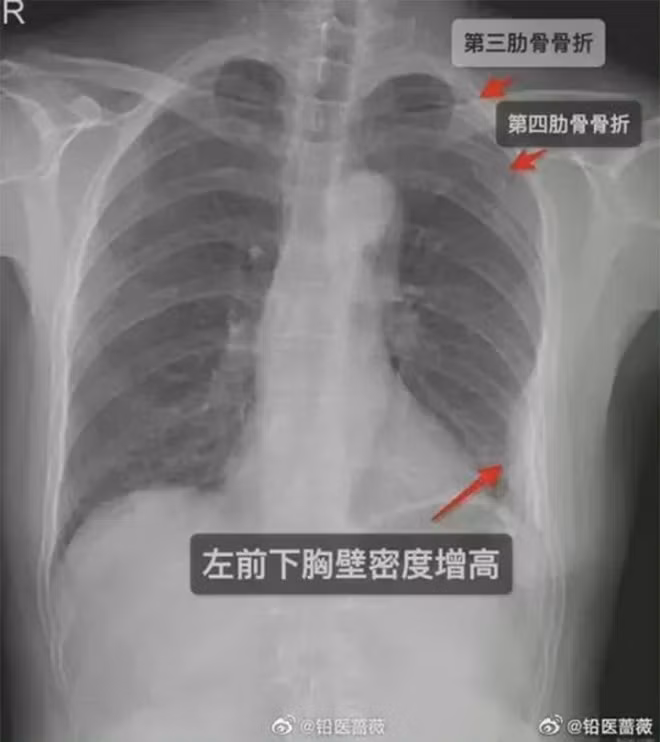

Đến ngày thứ 5 xảy ra vụ việc, người phụ nữ đã đến bệnh viện kiểm tra vì cơn đau không thuyên giảm. Kết quả khiến cô không khỏi sốc nặng, bác sĩ cho biết cô đã bị gãy 2 xương sườn trước bên phải và một xương sườn bên trái.